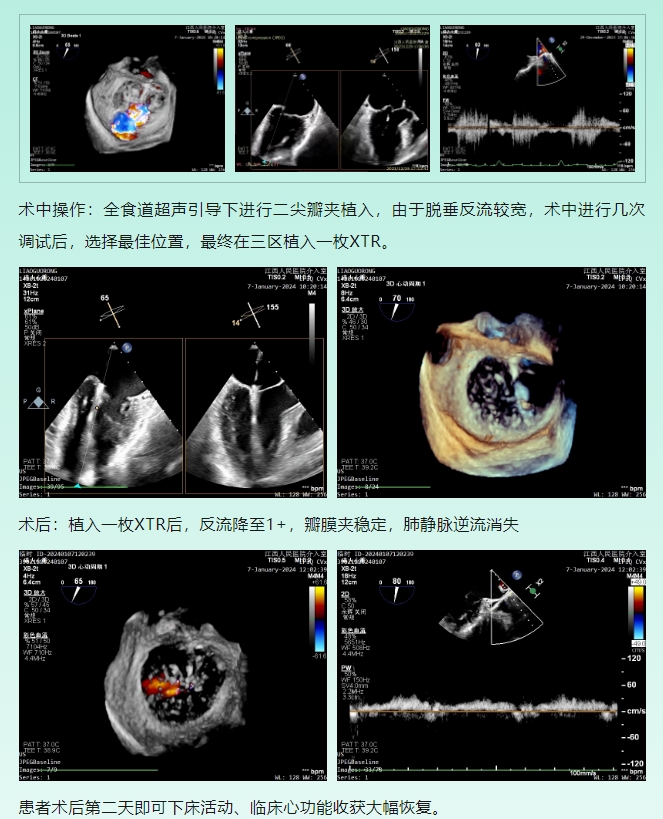

术前TEE评估:

(1)原发性二尖瓣反流,三区前叶广泛脱垂部分累及后交界,反流4+;

(2)三区前叶长度24mm,后叶长度17mm;二尖瓣瓣口面积5.93cm²;脱垂宽度15.4mm;平均跨瓣压差1mmHg,肺静脉频谱提示逆流明显。